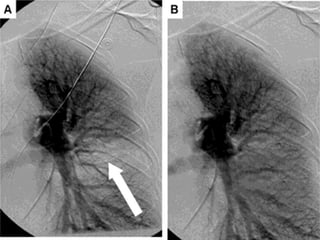

• Gold Standard

• Higher radiation

exposures

• Large contrast

bolus

Computed

Tomography

• Lower radiation

exposure

• 2/3rd are non-

diagnostic

• Safer in renal

patients

Ventilation/Perfusion

Scan

Stein PD. Am J Med. 2007;120:871-879 Anderson DR. Curr Opin Pulm Med. 2009;15:425–429

• #25 PIOPED II subgroup analysis showed increased rate of false abnormality when compared to CTPA